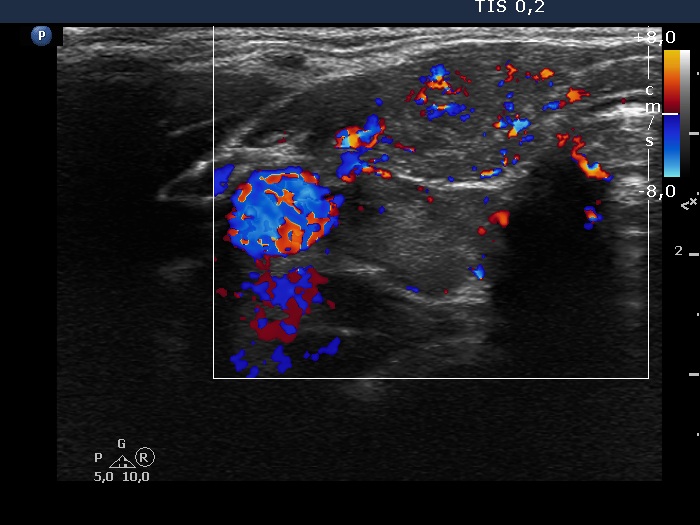

Right lobe, longitudinal scan

- There are two situations in Graves 'disease where circulation is increased. At the stage of disease activity and when hypothyroidism is observed with medication. In the former case, the blood flow is almost always increased, in the latter it can be decreased and increased.